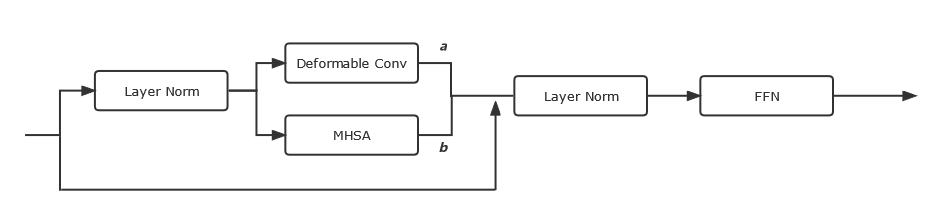

Besides, each layer also contains an ETB (seen in Fig. 4) to enable the UGformer to obtain both long-range dependencies and local context.

Inspired from [24], a single MHSA block is involved in ETB to extract long-range relationships and spatial dependencies. We engage DCs [5] parallel to MHSA to improve segmenting irregular LAs and quantifying LA scars. To make ETB adapt to both MHSA and deformable convolutions, a set of learnable parameters ( and see Fig. 4) are set to leverage both paralleling parts [19].